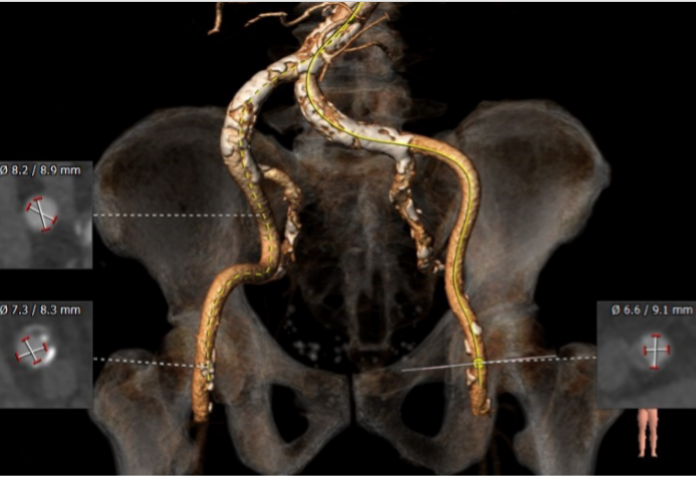

入路评估

1.股动脉直径可使用22F大鞘

2.在入路直径大于6mm且无扭曲的条件下,优先选择右侧股动脉